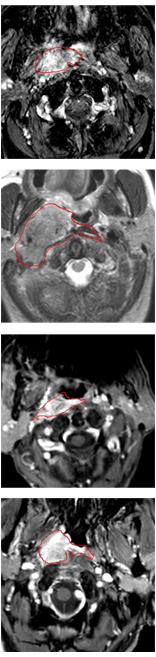

Currently, there is still no effort to fuse multi-modality MRI to develop an automatic segmentation system for NPC. According to researches of Popovtzer et al. [16], it should be a routine clinical practice to incorporate all kinds of MRI datasets in highly conformal radiation therapy to realize GTV delineation of NPC. For delineation of NPC, MRI is the perferred imaging modality for its superior soft tissue contrast [16, 3]. Moreover, MRI of different modalities data have different visual characteristics and various responses to different tissues and anatomical structures. For example, T1-weighted (T1) MRI is suitable for detecting skull base involvement and fat planes, while contrast-enhanced T1-weighted (CET1) MRI is used to identity tumor extent [3]. Figure 1 shows some examples of NPC response in T1, CET1 and T2-weighted (T2) MRI.

Refer to caption

Figure 1: Examples of slices from different MRI (T1, CET1 and T2), the contour of NPC is marked in red line. (a),(b) and (c) are slices from T1 , CET1 and T2 respectively.